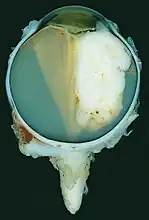

Gross and microscopic appearances of retinoblastoma are identical in both hereditary and sporadic types. Macroscopically, viable tumor cells are found near blood vessels, while zones of necrosis are found in relatively avascular areas. Microscopically, both undifferentiated and differentiated elements may be present. Undifferentiated elements appear as collections of small, round cells with hyperchromatic nuclei; differentiated elements include Flexner-Wintersteiner rosettes, Homer Wright rosettes,[25] and fleurettes from photoreceptor differentiation.[26]

Large exophytic white tumor with foci of calcification producing total exudative retinal detachment -

A retinoblastoma as seen in an eye removed from a 3-year-old female